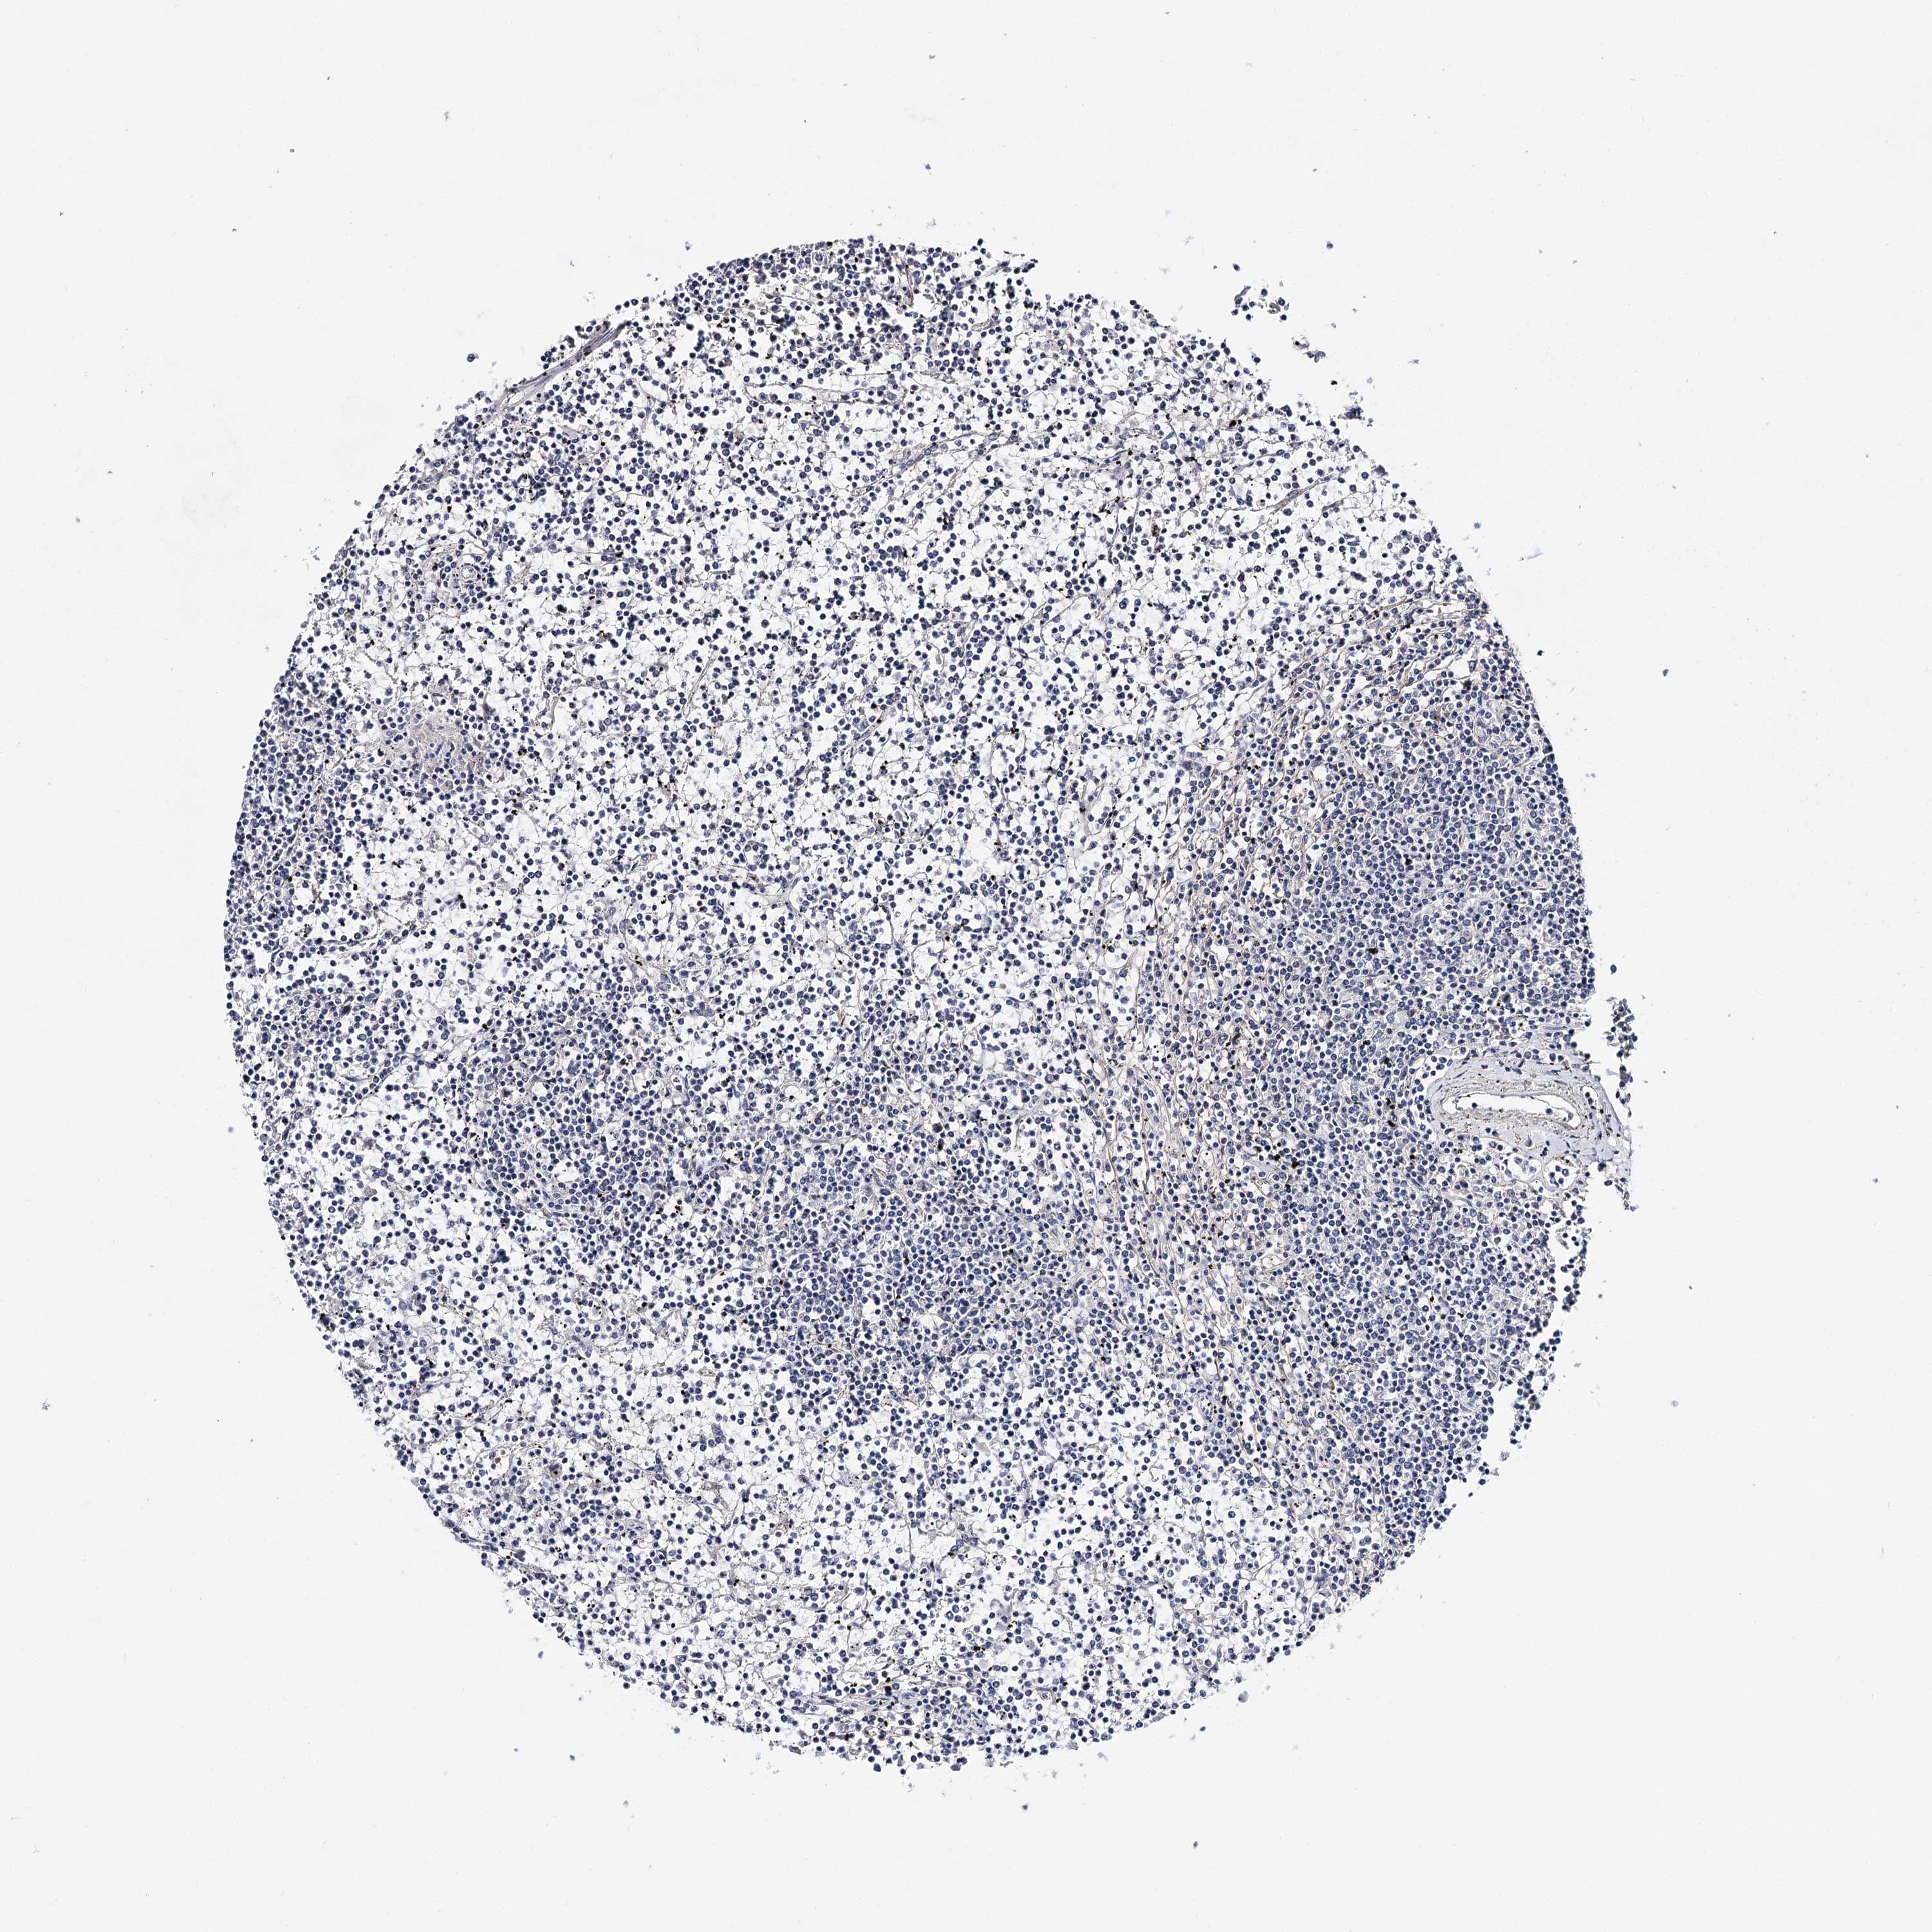

CANCER LYMPHOMA Show tissue menu

LYMPHOMA - Protein expressioni

A mouse-over function shows sample information and annotation data. Click on an image to view it in a full screen mode. Samples can be filtered based on level of antibody staining by selecting one or several of the following categories: high, medium, low and not detected. The assay and annotation is described here.

Each image is clickable and will lead to virtual microscopy that enables deeper exploration of all samples and also displays staining intensity scores, fraction scores and subcellular localization as well as patient and tissue information for each sample.

Antibody HPA037786

Hodgkin's disease, NOS

Malignant lymphoma, non-Hodgkin's type, High grade

Malignant lymphoma, non-Hodgkin's type, Low grade